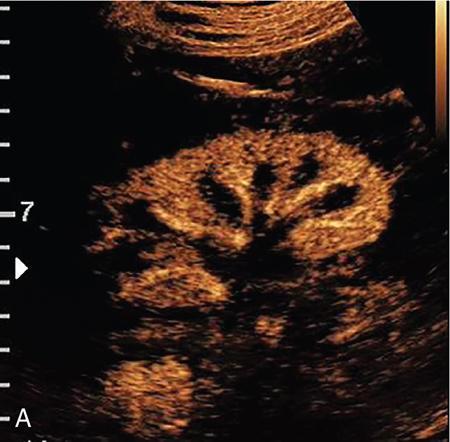

Drushi Patel CONTRAST-ENHANCED ULTRASOUND IN ADULT GENITOURINARY IMAGING Mridula Muthe Ultrasound is the initial screening examination for the evaluation of the renal morphology and suspected renal lesions due to its multiple advantages such as easy accessibility, bedside assessment, affordability and lack of radiation. Vascularity of the kidney and renal lesions can be studied with the use of colour Doppler ultrasound however, it provides information only about the macrovasculature. With the use of microbubble ultrasound contrast agents (UCAs) macro as well as the microvasculature can be studied. Contrast-enhanced ultrasonography (CEUS) is also more sensitive than Doppler ultrasound as it is not affected by blood velocity and angle of insonation of the ultrasound beam. In urology, the established applications of CEUS in adults include characterization of cystic lesions and differentiation between pseudotumours and solid lesions. Box 10.23.1.1 provides a list of European Federation of Societies for Ultrasound in Medicine and Biology (EFSUMB) recommended indications of CEUS in renal evaluation. EUROPEAN FEDERATION OF SOCIETIES FOR ULTRASOUND IN MEDICINE AND BIOLOGY (EFSUMB) RECOMMENDED INDICATIONS FOR USE OF UCA IN RENAL EVALUATION Renal ischaemia. Evaluation of solid renal lesions. Differentiation between solid renal lesions and pseudotumours. Characterization of complex cystic masses. Characterisation of indeterminate renal masses. Renal infections. Follow-up of nonsurgical complex masses. To improve lesion visualization in patients undergoing renal tumour ablation under US guidance and to detect residual tumour either immediately or after ablation. Isolated blunt moderate-energy renal trauma. Follow-up of trauma patients managed conservatively. Characterization of thrombus in renal vein and inferior vena cava. In patients with contraindications for CT- and MRI-based contrast media. Evaluation of lesions in transplant kidneys. Evaluation of ischaemia and vascular complications in transplant kidneys. Tumour response assessment to biologic therapy. Intracavitary CEUS for guiding percutaneous nephrostomy. Source: P.S. Sidhu, V. Cantisani, C.F. Dietrich, O.H. Gilja, A. Saftoiu, E. Bartels, et al., The EFSUMB guidelines and recommendations for the clinical practice of contrast-enhanced ultrasound (CEUS) in non-hepatic applications: update 2017 (long version). Ultraschall in der Medizin-Eur. J. Ultrasound 39 (02) (2018) e2–e44. CEUS involves the intravenous injection of UCAs consisting of gas microbubbles. These UCAs remain purely in the intravascular compartment as they are small enough to avoid filtration by the lungs and too large to enter the interstitial compartment. UCAs cause marked amplification of signals from the flowing blood, thus providing information about the microvasculature and parenchymal perfusion. Sonovue is a second-generation UCA and is the only UCA available in India. It consists of sulphur hexafluoride gas which is exhaled by the lungs and is surrounded by phospholipid monolayer which is metabolised by the liver, making it safe for patients with renal insufficiency. For renal evaluation, a dose of 1–1.5 mL of Sonovue is administered as a bolus dose followed by a 10 mL saline flush. CEUS is performed on machines with contrast-specific software’s using a low mechanical index (MI) technique. The use of a dual image display is beneficial for the evaluation of small lesions. A conventional B-mode ultrasound is first performed to acquire measurements, assess morphology and to detect focal lesions along with Doppler ultrasound to assess vasculature. However, due to limitations in the assessment of focal lesions, microvasculature, complex cysts, poor contrast between the lesion and cortex or medulla, it is preferable to perform a CEUS study for additional characterization. The enhancement pattern of the kidney is different than that of the liver due to the dual blood supply of the liver as opposed to afferent arterial supply and efferent venous drainage of the kidney. After an intravenous bolus of UCA, kidneys show intense enhancement. Contrast is first seen in the main renal artery, followed by its branches. CEUS has only two enhancement phases, that is cortical phase which lasts for 15–30 seconds and a parenchymal phase (enhancement of both cortex and medulla) for 25 seconds–4 minutes after UCA administration. The renal cortex enhances first, followed by the outer medulla which is followed by gradual enhancement of the pyramids (Fig. 10.23.1.1). During the washout phase first, there is a reduction in the medullary enhancement followed by a slower washout of the cortex. As kidneys don’t excrete UCAs, there is no opacification of the pelvicalyceal system. UCAs can act as a problem-solving tool in patients with renal failure as they are not nephrotoxic. Due to its excellent ability to depict renal vascularization, it can be used for detecting perfusion abnormalities. CEUS is useful for detecting vascular causes of renal function deterioration. Renal infarcts appear as wedge-shaped nonenhancing areas in all phases. Renal infarcts show a focal complete lack of parenchymal enhancement on CEUS whereas ischaemic areas show reduced enhancement. CEUS can confidently differentiate infarction from cortical necrosis by the demonstration of preserved hilar vascularity in the latter. Renal pseudotumours such as foetal lobulations, dromedary hump, parenchymal hypertrophy due to renal scarring and column of Bertini can be accurately differentiated from true tumours using CEUS. Pseudotumours show similar enhancement to the adjacent parenchyma and appear isoechoic on all phases while true tumours show different enhancement pattern on at least one phase (Fig. 10.23.1.2). True tumours will cause mass effect and distort the normal vascular architecture of the renal parenchyma whereas in pseudotumours the vascular architecture is preserved. In addition, the identification of medullary pyramids within the mass points towards it being a pseudotumour rather than a true mass. Cysts can be categorized according to the Bosniak classification using CEUS. Due to its superior spatial and temporal resolution, CEUS is considered superior to CT for detecting additional septations, wall or septal thickening and solid components (Figs 10.23.1.3–10.23.1.5). CEUS allows for real-time imaging of blood flow within the septae, wall or nodules within the cysts which may not be seen on CT or MR imaging. The sensitivity of CEUS is comparable to CT for the classification of renal cystic lesions as benign or malignant however, it is not as useful for staging. The follow-up of inoperable complex cystic lesions is better performed with CEUS rather than CT due to the absence of ionizing radiation. Complex cysts or masses with calcifications are not suitable for evaluation with CEUS. CEUS allows a detailed evaluation of the circulation in mass lesions as it demonstrates the macro as well as microvascular enhancement patterns. CEUS has more sensitivity than CT for detecting blood flow in hypovascular lesions. It can also be used to distinguish between complex cysts and solid lesions which remain equivocal on CT and ultrasound (B-mode and colour Doppler). CEUS is sensitive in identifying cystic areas, necrosis, debris and haemorrhage in small tumours that may be difficult to visualize on CECT and MR. Isoechoic lesions on conventional ultrasound are better characterized by CEUS (Fig. 10.23.1.6). Hyperdense renal lesions on noncontrast CT (NCCT) with HU values between 20 and 70 are better evaluated by CEUS which can classify these lesions as solid or cystic. CEUS can suggest the histological subtype of tumours. Clear cell carcinomas show heterogeneous hyperenhancement in the cortical phase and rapid washout along with a peripheral enhancing rim or pseudocapsule seen during the parenchymal phase. Papillary carcinoma shows progressive heterogeneous enhancement during the cortical phase and displays hypoenhancement as compared to the cortex on all phases. Malignant renal vein thrombus will show enhancement as compared to bland thrombus on CEUS. Tumours that are smaller than 3 cm commonly show homogeneous enhancement, regardless of their histologic subtype. Differentiation between angiomyolipoma, renal cell carcinoma and oncocytoma is not always possible. Although, CEUS has excellent sensitivity for the detection of malignancy, it has a higher false-positive rate as compared to CECT. Hence, combined use of CEUS for its high sensitivity and CECT for its high specificity may be performed for an accurate diagnosis. CEUS is effective in patients with complicated pyelonephritis, for identifying inflammatory parenchymal involvement, characterized by round or wedge-shaped hypovascular parenchymal areas, most conspicuous during the late parenchymal enhancement phase. An abscess is seen as a nonenhancing area, with or without peripheral or septal enhancement. CEUS can also be used for the follow-up of renal abscesses. All the aforementioned indications of CEUS in native kidneys also apply to renal transplants. Infarction, vascular complications such as arterial and venous thrombosis can be detected. Quantitative CEUS for assessment of graft dysfunction is a subject of active research. CEUS can be used as an alternative to CT especially in children with isolated blunt moderate energy injuries who are hemodynamically stable. It can also be used in the follow-up of conservatively managed trauma patients and in renal impairment. During Focused Assessment with Sonography for Trauma (FAST), the examination should begin with the kidneys as they have a fleeting enhancement. The kidneys are studied in the arterial phase with two separate doses administered for either kidney during FAST. On CEUS, lacerations, hematomas, and infarcts are seen as nonenhancing areas on late-phase images whereas contusions may show faint enhancement. Pseudoaneurysms and active bleeding are diagnosed on the arterial phase. Crucial complications such as devascularized parenchyma and acute cortical necrosis can also be diagnosed on CEUS. Pelvicalyceal system injury cannot be detected by CEUS as UCAs are not excreted by the kidneys. CEUS can be performed in conjunction with percutaneous ablation therapies. Preablation evaluation with CEUS is essential to assess lesion vascularity and to compare pre and postprocedure tumour viability. Also, the identification of a pseudocapsule predicts improved ablation efficacy. CEUS has demonstrated high sensitivity, specificity and accuracy for the early detection of residual unablated tumour. Dynamic contrast-enhanced ultrasound is a useful tool for early identification of responders and nonresponders, enabling tailoring of the treatment regimen. It is performed by two methods – Bolus injection of a UCA with time-intensity curve analysis (commonly used) and intravenous injection of UCA with disruption–replenishment analysis. In patients with chronic kidney disease, the contrast enhancement is less intense and fades earlier as compared to a normal kidney. CEUS aids in characterizing renal lesions in patients with renal failure. Characterization of lesions with indeterminate appearances in patients with renal dysfunction, on conventional US prevents unnecessary further evaluation with contrast-enhanced CT or MRI and further deterioration of the renal function as well as unwarranted investigations. CEUS nephrostomogram can be performed after percutaneous nephrostomography to confirm the correct positioning of its tip, detect the site of obstruction and to diagnose complications. UCAs can be safely administered in patients with minimal risk. They can be safely administered in patients with renal insufficiency as they are not excreted by the kidneys. Prior laboratory tests are not indicated as they are not nephrotoxic and don’t interact with thyroid function. Most adverse effects are mild such as nausea, headache, chest discomfort, chest pain and resolve spontaneously. The contraindications include known hypersensitivity, patients with right-to-left shunts, severe pulmonary arterial hypertension (pulmonary arterial pressure >90 mm Hg), uncontrolled systemic hypertension, and respiratory distress. The rate of anaphylactic reactions is significantly lower than iodinated contrast media and comparable to gadolinium-based contrast agents. Caution should be exercised in patients with severe acute coronary disease and in patients with unstable angina. CEUS is a rapidly evolving technique, can be conveniently performed as an extension of conventional ultrasound and acts as a valuable tool in the characterization of indeterminate renal lesions, especially when the lesion is small. The advantages of CEUS include quick assessment, real-time imaging, high contrast resolution, excellent safety profile, lack of ionizing radiation, great repeatability, and most importantly, ideal for contrast evaluation in patients with deranged renal function. DUAL-ENERGY AND SPECTRAL IMAGING IN GENITOURINARY SYSTEM Aditi Chaitanya Gujarathi-Saraf Dual-energy CT (DECT) also known as ‘spectral imaging’, was first conceptualized in the 1970s. However, the clinical applications of DECT have recently emerged as owing to improvements in postprocessing techniques. The development of a single-detector, single-source DECT (ssDECT) with the capability for rapid alternation between two peak voltage settings (‘fast switching’) and a dual-detector, dual-source DECT (dsDECT) system in last few years have made possible various applications in solving clinical problems. In DECT, the simultaneous use of two different X-ray beam energy settings (80 and 140 kVp) allows the differentiation of materials on the basis of their attenuation characteristics (material density). There are two major applications of DECT in genitourinary system. First being characterization of renal calculi to differentiate those containing uric acid (UA) from those which do not. The other application is to characterize small renal masses which include differentiating complex cysts from renal tumours, detection of solid growth in PCKD patients and detection of residual tumour after thermal ablation of a renal neoplasm. The principle of DECT imaging is based on the differential absorption of X-ray energy at variable kVp settings. In DECT, two energy levels (typically 80 and 140 kVp) are used to acquire images that can be processed to generate additional datasets. Thus, a tissue or any material in the body shows different degrees of attenuation when scanned at different X-ray energies. Conventional CT numbers (attenuation measurements in Hounsfield units) are related to the linear attenuation coefficient of a particular material. The unique linear attenuation coefficients obtained by imaging at two different energies can be used to discriminate between different materials (e.g. fat, calcium, iodine and water). The characterization of material on DECT depends on their CT number ratio (CTR) also called dual-energy ratio. DE RATIO = CT number of a given material in the low-energy image CT number of the same material in the high-energy image DECT and spectral CT can be performed by three techniques (Fig. 10.23.2.1): Two sets of material-specific images are created to detect the presence or absence of a material. The two basic materials selected should have significant difference in mass attenuation coefficients and atomic number. The two commonly selected pairs are: Iodine-specific images are most commonly used in the clinical practice. When iodine is paired with water, two separate image data sets are generated. On water density image, the voxels that show change in attenuation due to presence of iodine are removed. These are instead represented on iodine density images. Thus, virtual unenhanced images are generated which resemble the conventional unenhanced images. Renal calculus disease is a common disease affecting approximately 10%–14% of population in India commonly affecting 31–45-year-old patients. Accurate diagnosis of composition of renal calculi is crucial as the frequency of prevalence and recurrence rate of renal calculi is high in most states of India. The obstructing calculi can lead to obstructive uropathy, pyelonephritis, urinary sepsis with nearly 50% of the patients being affected by renal failure. There are multiple compositions of renal calculi, most common being calcium oxalate (70%), calcium phosphate (20%), uric acid (8%) and cystine (2%). In general, UA calculi have lower attenuation values than nonuric acid calculi (i.e. struvite, cystine and calcium) on conventional CT. However, it may be difficult to distinguish between the two due to overlap in attenuation values. Here DECT becomes a problem-solving tool as it uses the two-material differentiation approach. Thus, in addition to size and location, DECT provides information about the composition of calculi to the urologist. DECT has high sensitivity of 88%–100% and high accuracy of 93%–100% to differentiate UA calculi from nonuric acid UA calculi. This is of utmost clinical importance as UA calculi can be treated medically whereas non-UA calculi require invasive methods of treatment such as extracorporeal shockwave lithotripsy (ESWL) or percutaneous nephrolithotripsy (PCNL). In clinical practice, NCCT scan of KUB region is performed at 80 and 140 kVp to generate two image datasets and obtain the DE ratio. A cut-off value of DE ratio of 1.2 is used to differentiate UA calculi from non-UA calculi (Fig. 10.23.2.2). Following flow chart shows differentiation of renal calculi based on DE ratio.